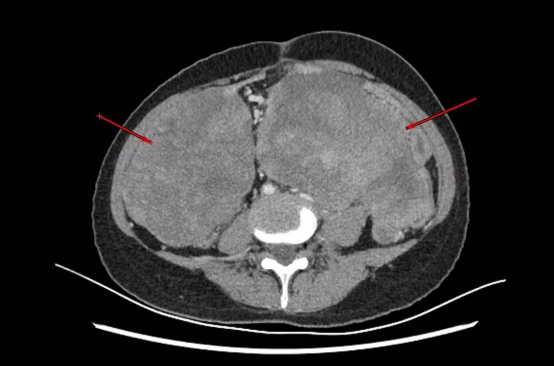

醫生向劉女士詢問病史與檢查後,從CT上發現劉女士的腹腔裡有多個腫瘤,而且最大的腫瘤直徑約23厘米,有如排球這麼大。其他大大小小的腫瘤布滿著整個盆腔與腹腔,甚至已經壓迫腹腔裡的內臟器官,如不儘快切除就會危及生命。

醫生表示,在手術的過程中,劉女士的腹腔與盆腔內的腫瘤已經佔據大面積無法推動,導致手術空間非常狹小。且劉女士之前還曾進行過3次腹部手術,有著嚴重的腹腔粘連,在分離過程中創面滲血嚴重,這些情況的發生為手術增加了難度。